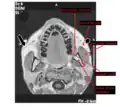

The left masseter muscle (red highlight), partially covered by superficial muscles such as the platysma muscle (below) and both the zygomaticus major and minor muscles